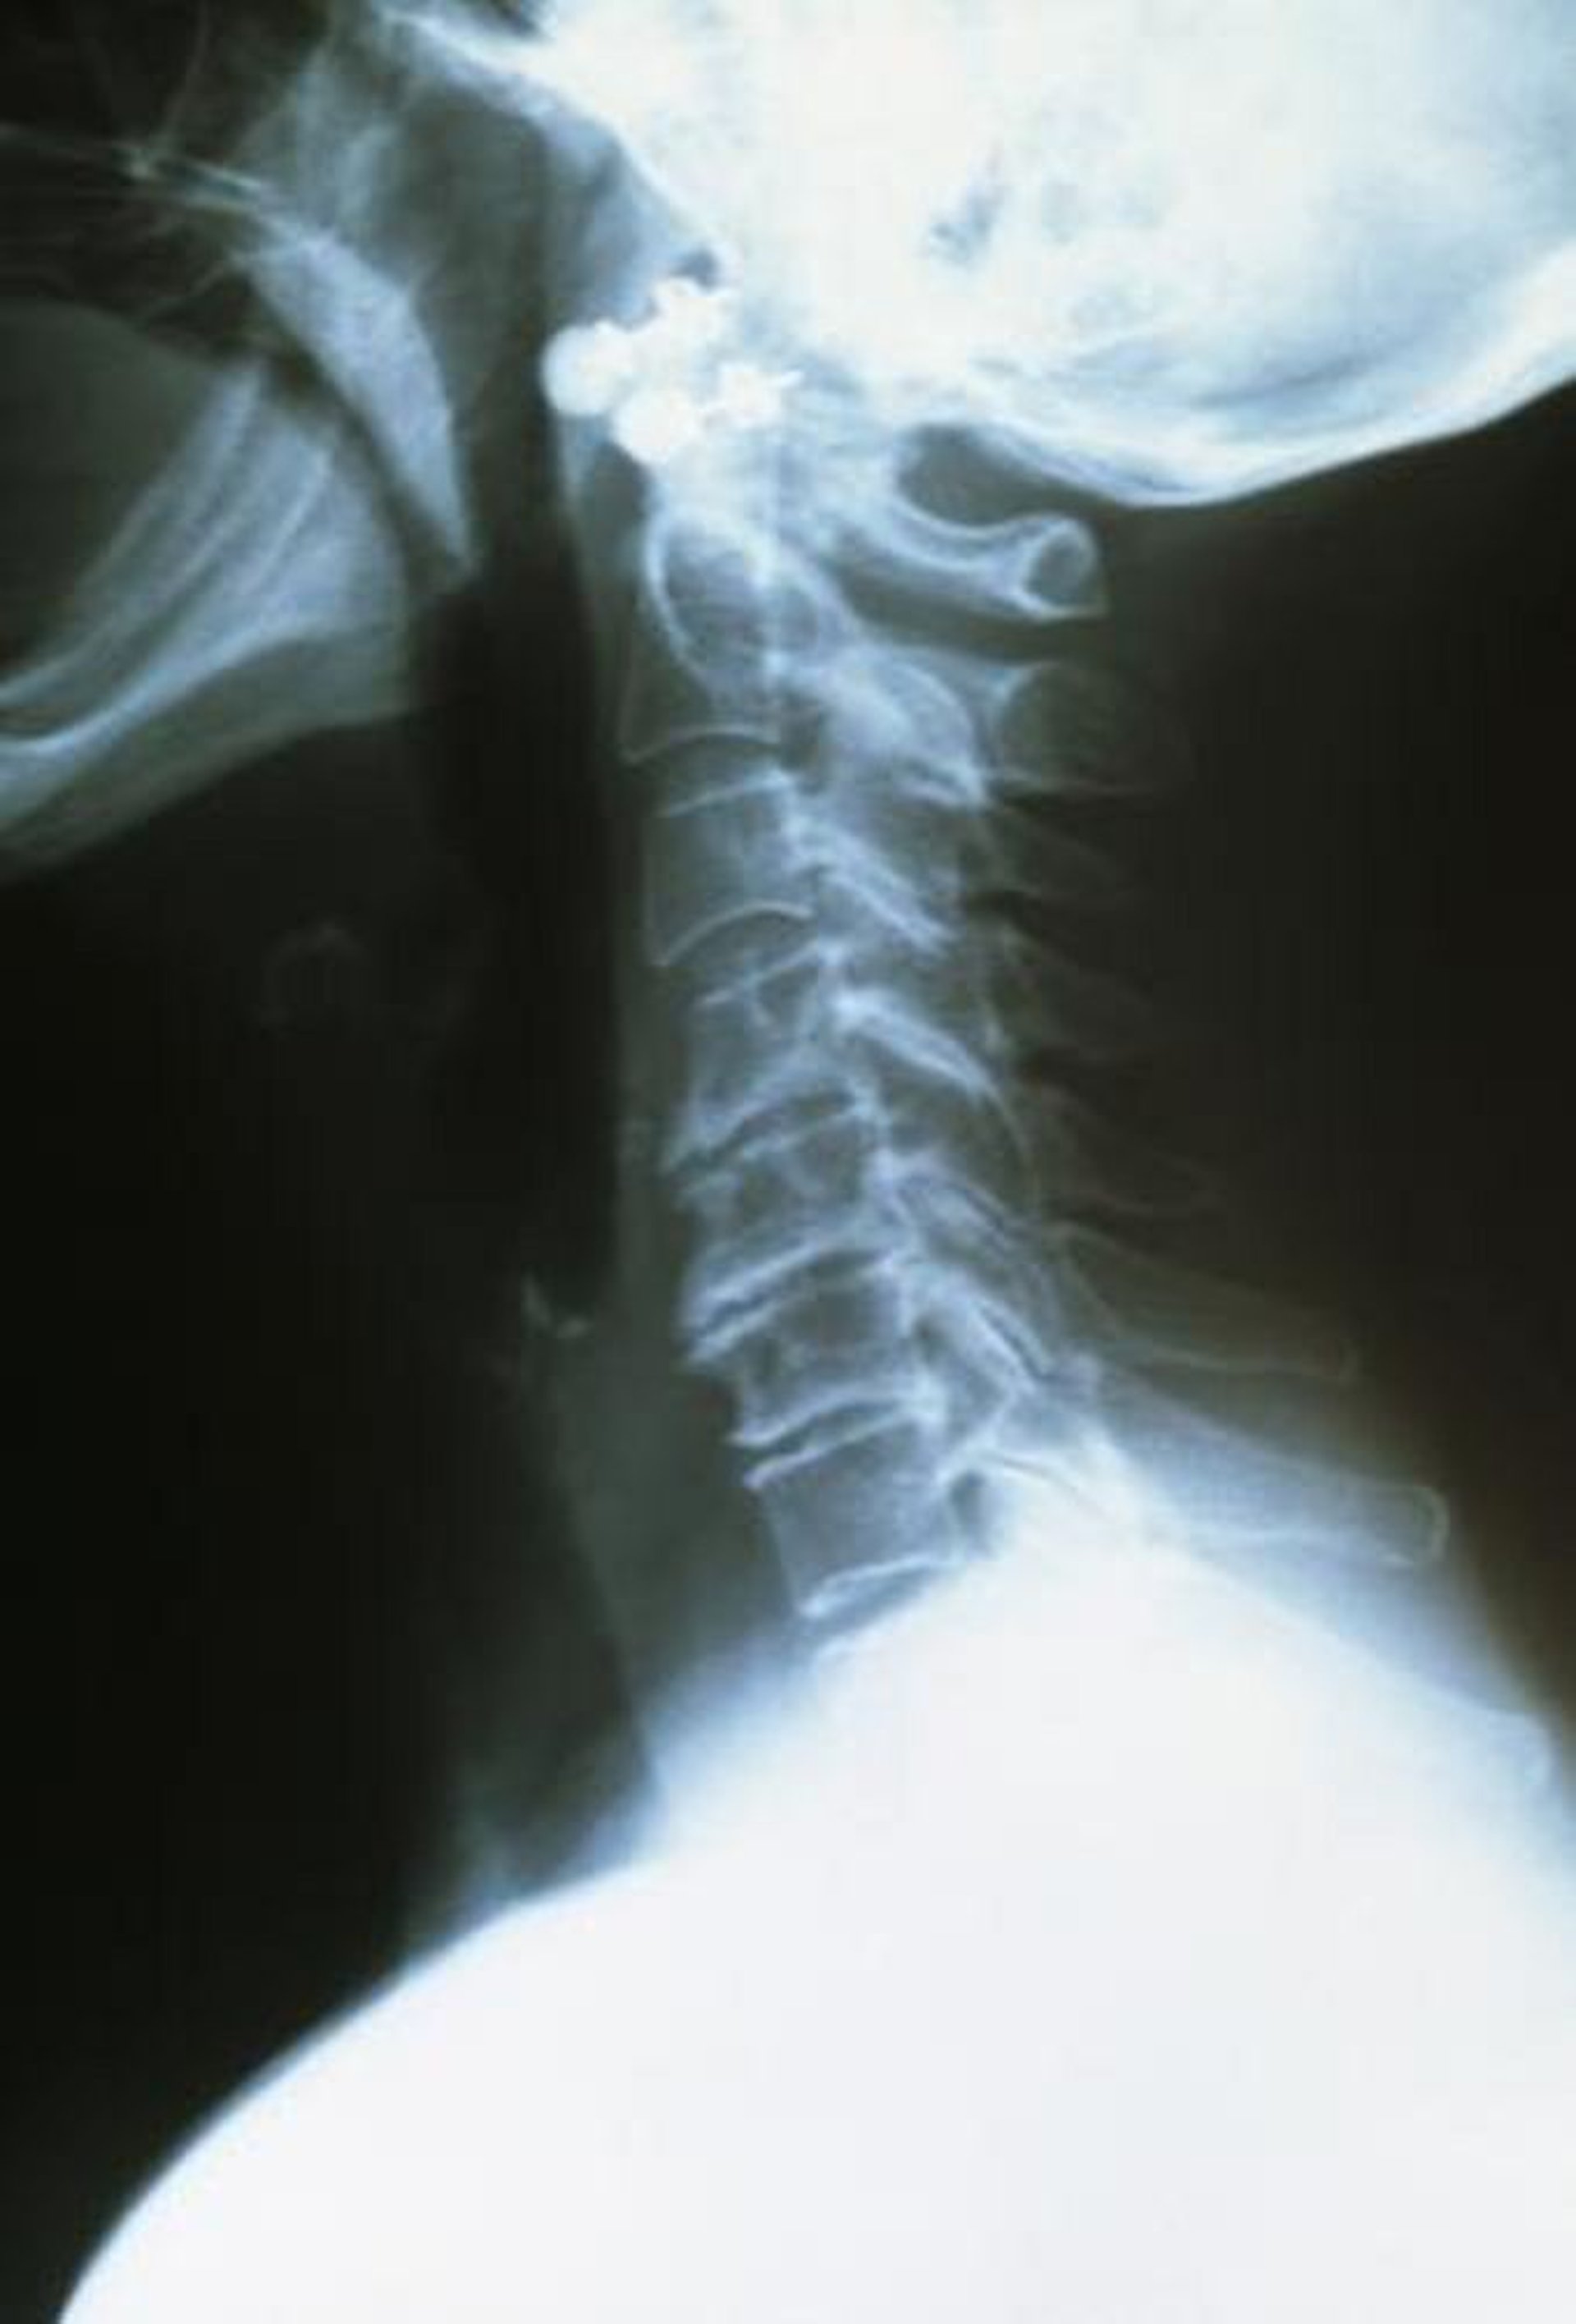

Thoái hóa cột sống cổ

Các đốt sống cổ trên khỏe mạnh, đều nhau và có viền nhẵn. Các đốt sống dưới khớp gần nhau hơn và có các cạnh thô và rách.